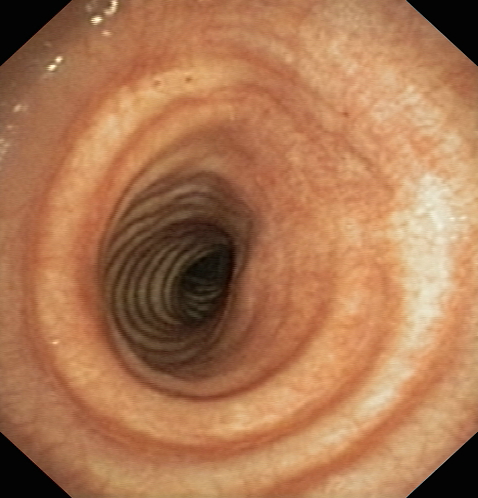

Фибротрахеобронхоскопия: Рак трахеи до и после проведения внутрипросветной брахитерапии с синхронной полихимиотерапией